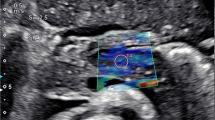

Conventional B-mode and 2-D SWE examinations were performed using LOGIQ P9 GE ultrasound system (GE Healthcare, Milwaukee, WI) using a 3.5- to 5-Mhz convex ultrasound transducer for all patients and controls. Examinations were performed and interpreted by two experienced radiologists (S.S.M. with 11 years’ experience and K.S.S. with 10 years’ experience) blinded to each other and to patients’ clinical and laboratory findings. The radiologists assessed patients separately and the mean score of both radiologists’ readings was taken for each patient.

The ultrasound transducer was placed in the epigastric region to visualize the entire pancreas. The pancreas was demonstrated in B-mode first, then 2-D SWE was performed in elastography display mode allowing 2-D elastography to be obtained. The ROI was placed on the pancreatic body ensuring that no blood vessels, capsule or pancreatic duct was located within it. The body was distinguished from the head by the confluence of the splenic and superior mesenteric veins. The tail was defined as the structure opposite the medial margin of the left kidney extending to the hilum of the spleen (identified by the splenic artery and vein) [1, 29].

The SWE measurements were automatically reported by the ultrasound machine by measuring 12 readings of elasticity at the ROI and calculating their median. Unacceptable shear wave measurements based on location or artifact were repeated. Reliable shear wave measurements were those with interquartile range (IQR) less than 30%.

Using conventional B-mode, no gross difference was found in the pancreatic echogenicity, homogeneity, contour and capsule sharpness between the studied children with type 1 diabetes and controls. Moreover, no pancreatic focal lesions or ultrasound evidence of pancreatitis was found in any of the subjects.

The mean SWE of the studied children with type 1 diabetes was 5.96±1.65 Kpa (range: 3.87–9.5), while that of the controls was 5.57±0.27 Kpa (range: 5.15–5.92), with no significant difference between the two groups (P=0.105). However, upon comparing the SWE between the studied children with recent-onset type 1 diabetes, those with long-standing type 1 diabetes and controls, a significant difference was found between the three groups (P<0.001). SWE was found to be highest in those with long-standing type 1 diabetes and lowest in those with recent-onset type 1 diabetes (P<0.001) (Table 2, Figs. 1, 2 and 3).

Shear wave elastography and diabetes complications

As shown in Table 3, SWE was significantly correlated with the frequency of severe hypoglycemia (P=0.005), HbA1C (P=0.03), low-density lipoproteins (P<0.001) and cholesterol (P<0.001). In addition, it was correlated significantly with diabetic neuropathy (P=0.04) and with diabetic nephropathy (P=0.05) (Fig. 4). Multivariate logistic regression analysis revealed that SWE was independently related to HbA1C (P<0.001) and the frequency of severe hypoglycemia (P=0.003) (Table 4).